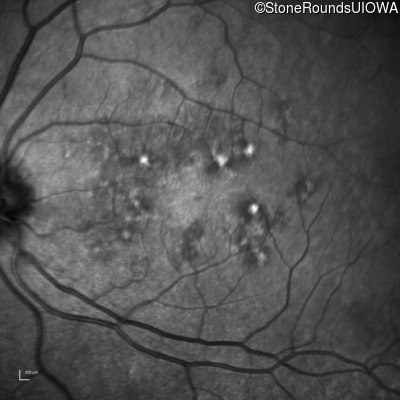

Infrared Fundus Photograph - Right - 20/20 -1

Exemplar

Infrared Fundus Photograph - Right - 20/16 -1